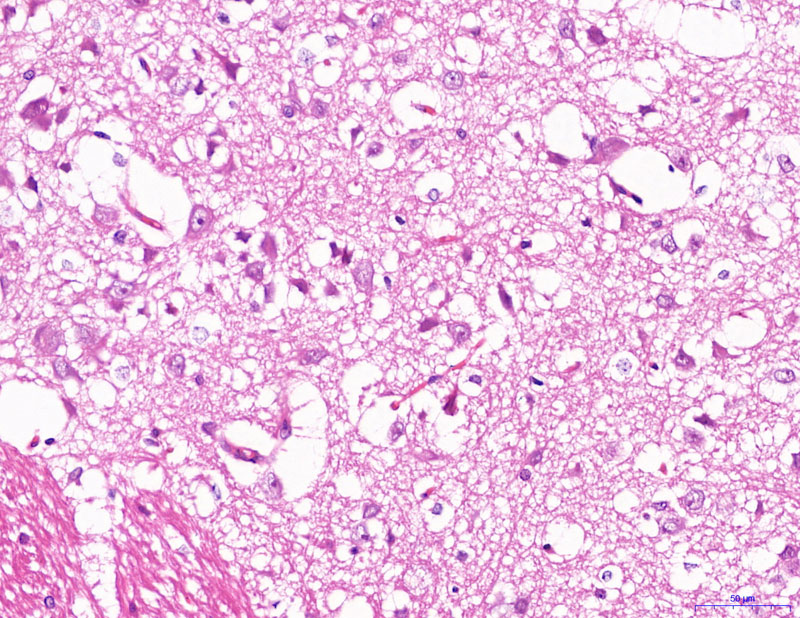

給藥-400

模型-400

正常-400